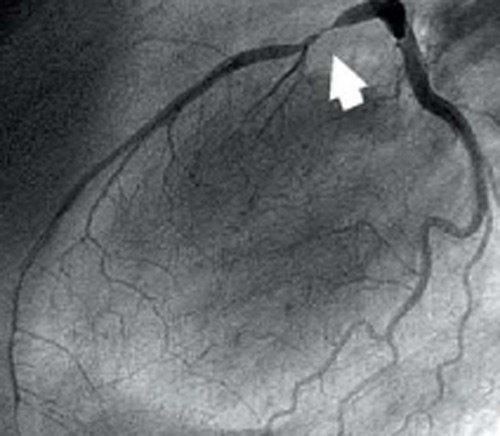

Коронарография это вид обследования, а не операция. Если при ней обнаружится не проходимость или стеноз тогда только ставят шунт или стент.

Маме делали и ставили стенды в 2011,2013 году,стенды потом тоже проверяют коронарографией.год назад сделали шунтирование т.к.стенды тоже начали забиваться.коронарография делается на основе йода и да после есть риск в первые сутки вроде врачи об этом говорят и дают кроворасжижающие лекарства,но эта процедура спасает жизни людей во время выявляет стеноз сосудов.здоровья вашему папе.